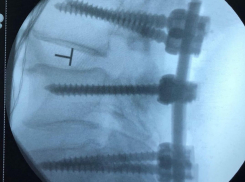

Общество Волгоградские врачи спасли мужчину после 5 неудачных операций в США

20.12.2021

Он уже не мог ходить